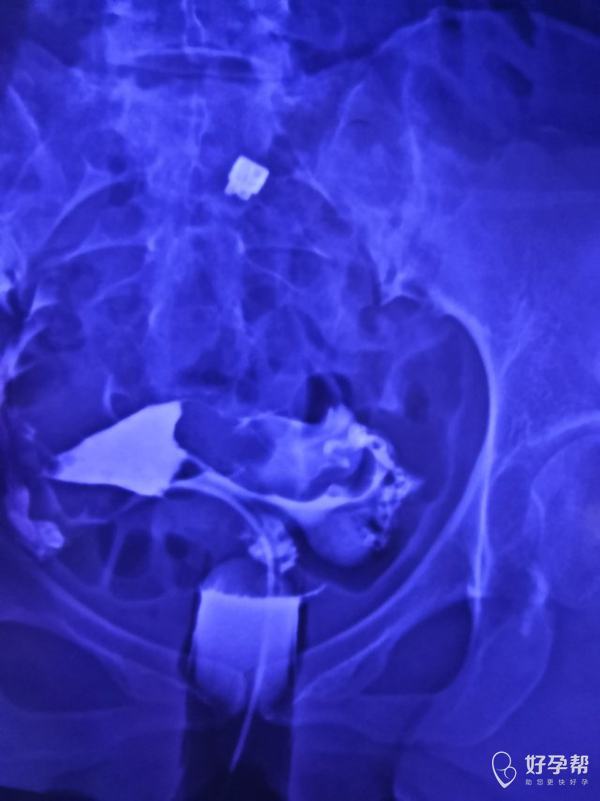

这种必须做手术么还是取了胚胎不是非要做

这个手术不是非得要马上做,需要根据你的年龄、生育计划等来综合评估并权衡利弊后再决定是否需要手术以及什么时候做。如果是做试管通常为了避免输卵管积液及炎症因子逆流至宫腔影响胚胎着床等,会行输卵管结扎等手术,这个手术通常在移植前完成